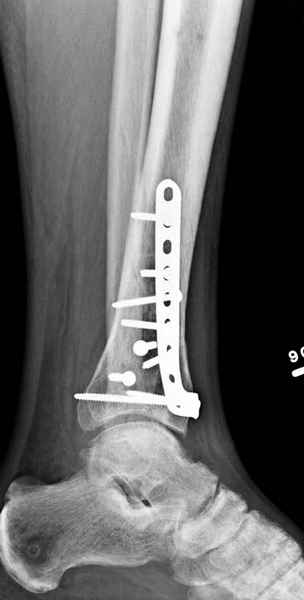

3. стабилизировать наружный опорный комплекс голени и предотвратить вальгусную деформацию голеностопного сустава. Конечно, данная проблема не очень актуальна, или вовсе не актуальна для 43С1, но для повреждений типа 43С2,3, особенно в случаях, когда метафизарный дефект потребовал пластики, а пластину пришлось уложить по медиальной стороне - остеосинтез малоберцовой кости является крайне необходимым - привожу характерный пример.

Но перелом малоберцовой кости может быть и много проксимальнее, и его так же приходится фиксировать из этих же соображений. И особенно, если пациент полный. Из отечественных хирургов на возможность развития такого осложнения - вальгусной деформации голеностопного сустава ч/з 2-3 месяца после операции при переломах типа 43С2 в отсутствии фиксации малоберцовой кости одним из первых указал Виталий Дрягин из ГКБ №3 Челябинска ещё в конце 90х.